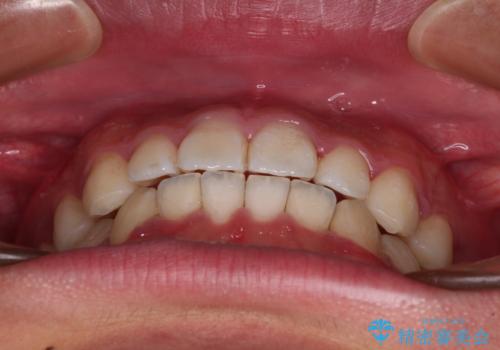

インビザライン・ライトは、製作できるアライナーの枚数に制限があるため、移動可能な量に限りがあります。

一方で、半年から1年程度で治療を終えることができるため、軽度の歯列不正の患者様には大変お勧めです。